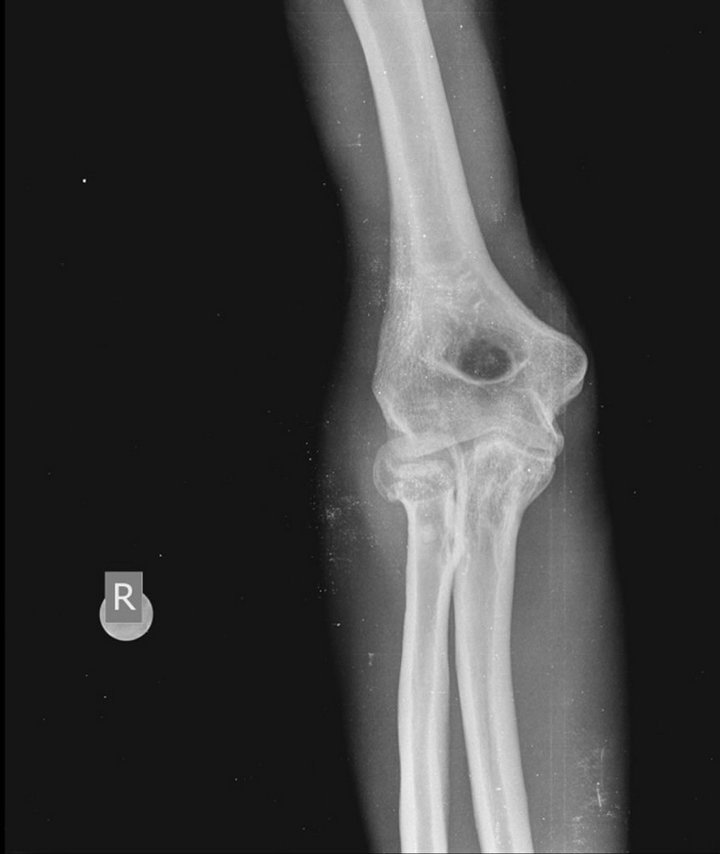

x ray of a Synovial chondromatosis elbow Stock Photo Adobe Stock Synovial Chondromatosis Elbow synovial chondromatosis most often occurs in the knee, followed by the hip, elbow, and shoulder. The condition most often occurs in patients between the ages of 30. synovial chondromatosis is a rare benign proliferative condition with metaplasia of the synovial membrane resulting in a monoarticular arthropathy characterized by newly formed foci of cartilage. primary synovial chondromatosis is. Synovial Chondromatosis Elbow.